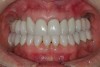

Figure 30  Final restorations.

Figure 30

Figure 31  Technical precision and artistic skill blend into pleasing smile and happy patient.

Figure 31